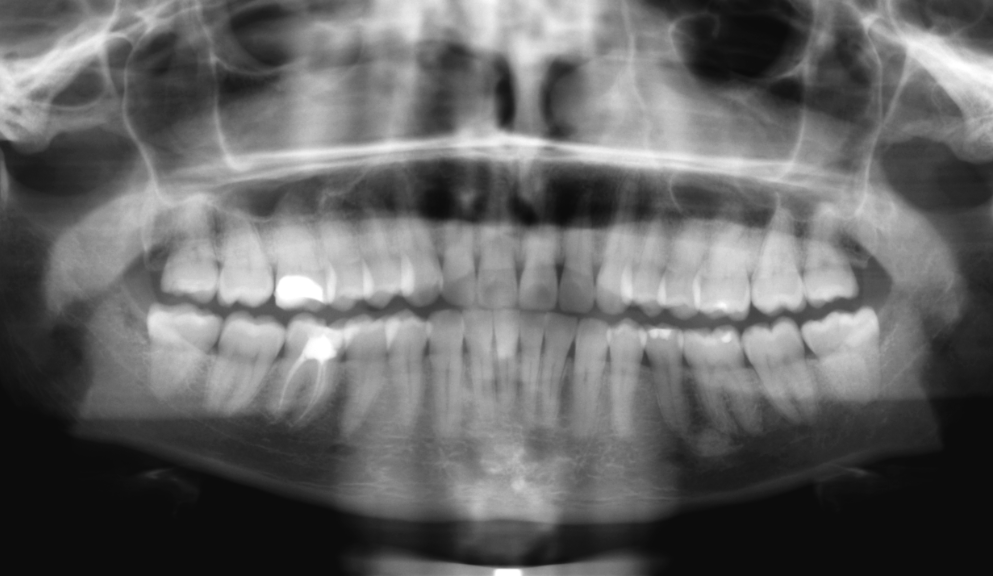

Рентгенография небного шва: Медицинские исследования и диагностика